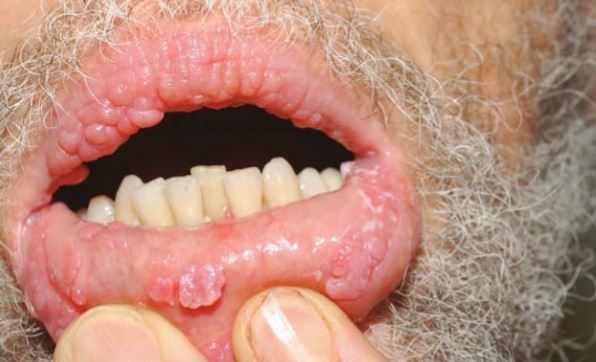

LİKEN PLANUS

Hastalığın kesin nedeni bilinmemekle birlikte, çevresel faktörler ve otoimmün bozukluklarla ilişkili olduğu düşünülen, ağız ve genital bölge başta olmak üzere vücudun çeşitli bölgelerini tutabilen enflamatuvar bir deri hastalığıdır. Kaşıntılı bir kızarıklığa sebep olur. 5p bulgusu. 1)pruritik 2)poligonal 3)purple 4)papül 5)parlak veya planar.

CloseLİKEN PLANUS

Hastalığın kesin nedeni bilinmemekle birlikte, çevresel faktörler ve otoimmün bozukluklarla ilişkili olduğu düşünülen, ağız ve genital bölge başta olmak üzere vücudun çeşitli bölgelerini tutabilen enflamatuvar bir deri hastalığıdır. Kaşıntılı bir kızarıklığa sebep olur. 5p bulgusu. 1)pruritik 2)poligonal 3)purple 4)papül 5)parlak veya planar.